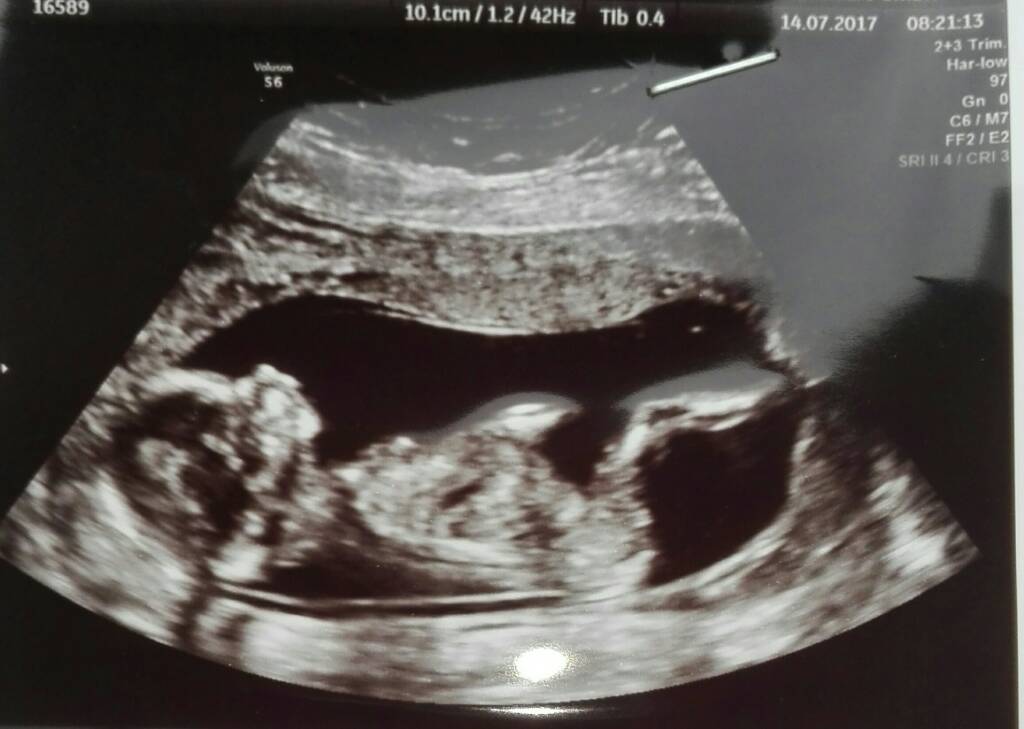

Zosia jest Zosią nic Jej nie wyrosło

ma się kwitnąco. Tylko z tego wszystkiego nie wiem ile mierzy. Krwiak się wchłonąl. Plamienie jest od odklejajacej sie owodni i pewnie się utrzyma do 16tc, ale w takim miejscu, że nie zagraża Małej a ja najlepiej leżeć mam